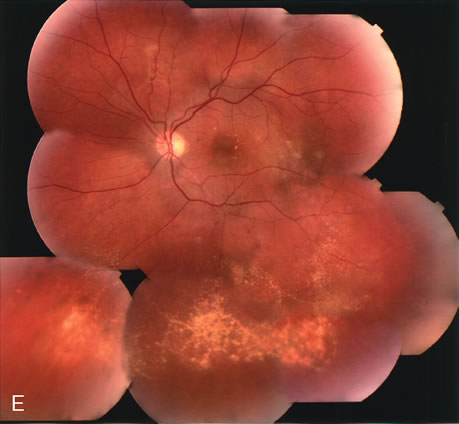

Fig. 14. A. Color photograph of the right eye shows a ramified pattern of choroidal vascular abnormality irradiating from the peripapillary area toward the macula. The dilated vascular channels end with bulging polyp-like structures. A larger, orange, saccular dilation is seen inferior to the macula (white arrow); leakage of fluid from this vascular abnormality results in serosanguineous pigment epithelium detachment (black arrows). B. The corresponding fluorescein angiogram composite highlights the vascular lesion in the peripapillary area and the serosanguineous detachment of the pigment epithelium that extends inferiorly and temporally off the macula.